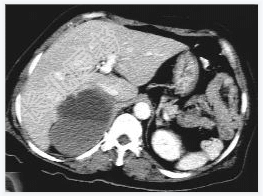

- [材料题] 女性,59岁,胸闷、头晕2天,呈持续性,伴呕吐,以进食后明显。发现“高血压”10年,“糖尿病”2年。体格检查:血压70~210/30~120mmHg。

- 简答题3、右肾上腺嗜铬细胞瘤囊变的定义是什么?

- 简答题4、右肾上腺嗜铬细胞瘤囊变的临床意义是什么?

- 简答题5、右肾上腺嗜铬细胞瘤囊变的诊断和治疗上需要注意哪些事项?